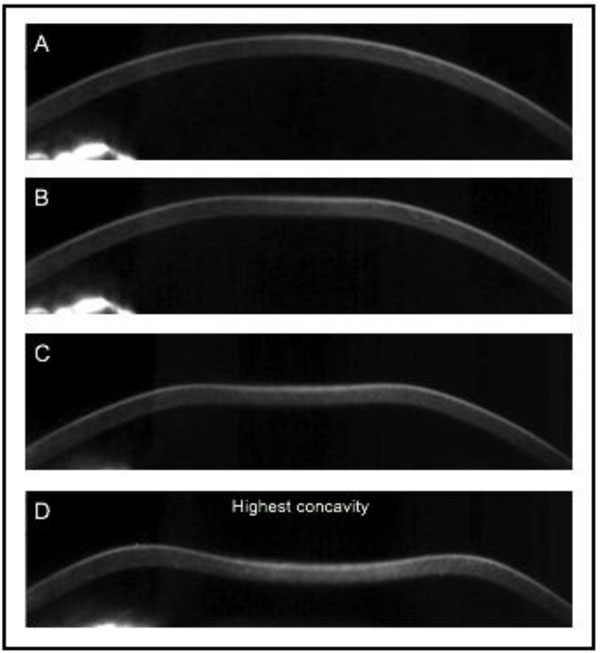

(Oculus, Wetzlar, Germany) was later presented as an alternative device for in vivo acquisition of the corneal biomechanical properties. It combines non-contact tonometry with high-speed Scheimpflug visualization of the corneal deformation during the symmetrically metered air pulse Fig. (2). With 4330 frames per second, the Corvis ST records the dynamic deformation and determines velocity, length, and time lapse during applanation and highest concavity Table 1. The initial Corvis ST software version presented a limited number of parameters; later new variables followed describing the inward and outward applanation in further detail.